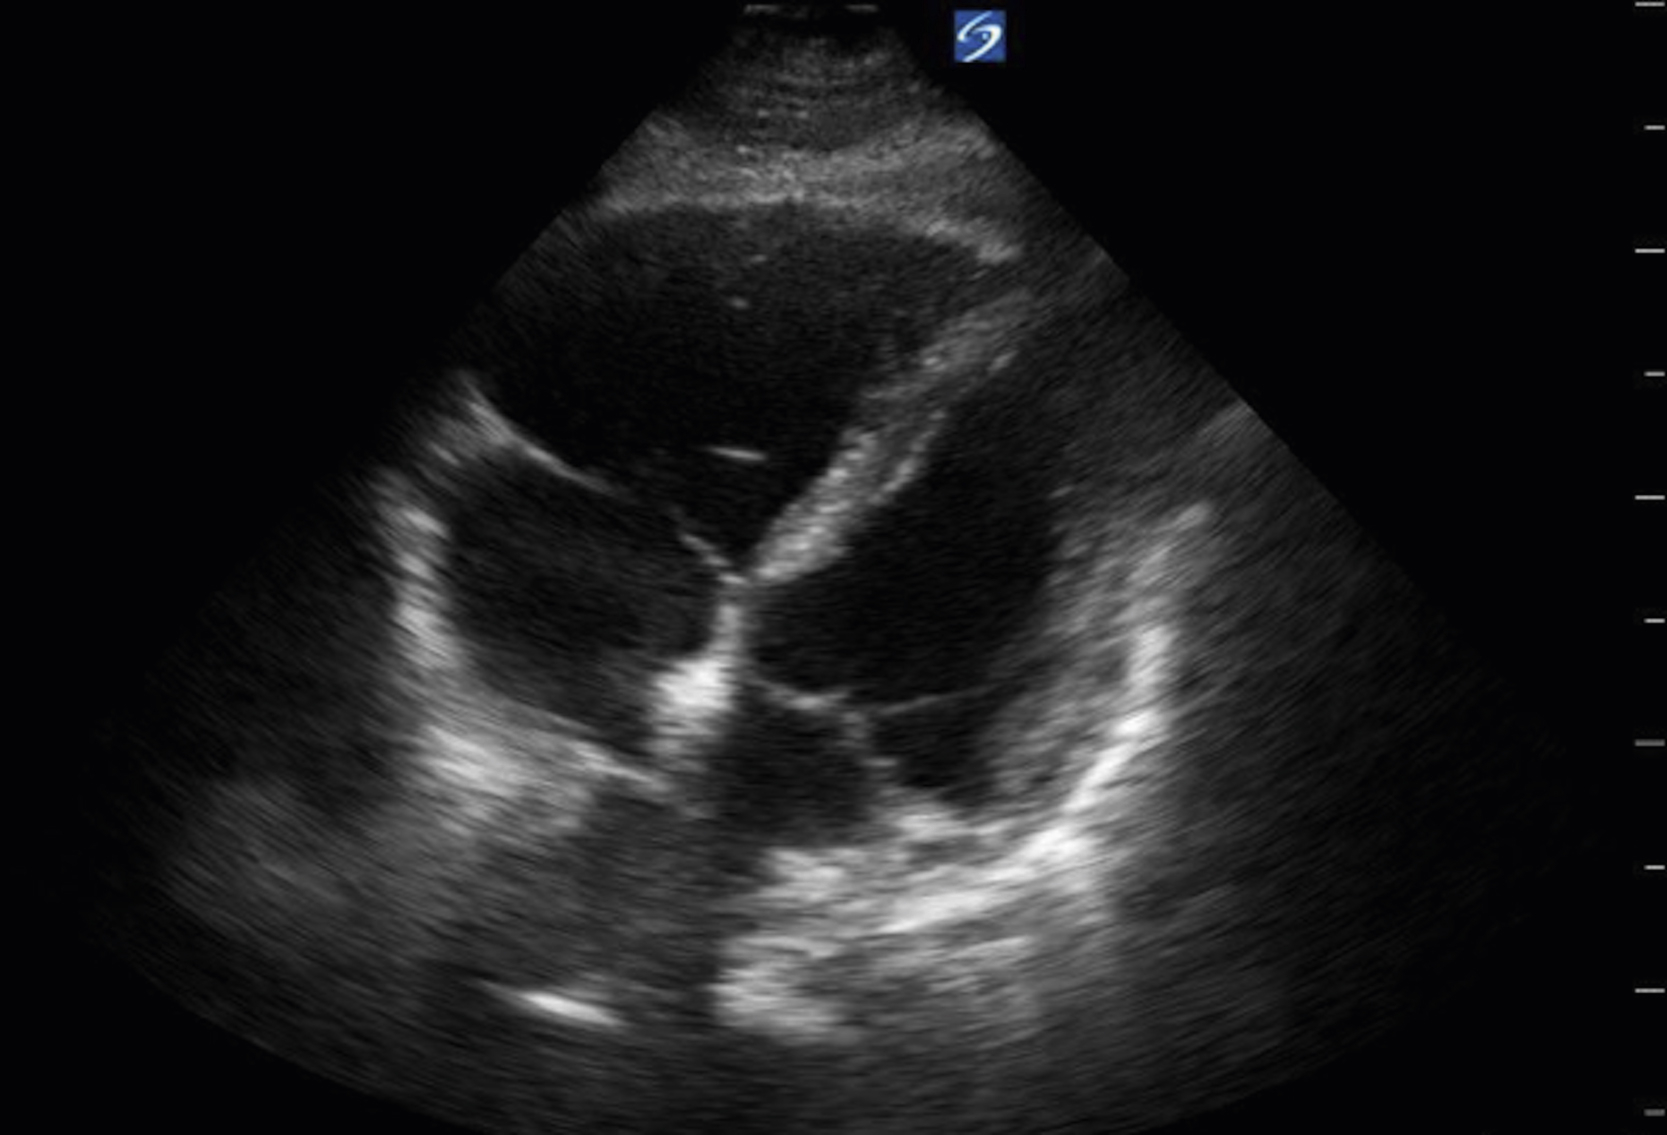

RV assessment is another useful tool for the emergency clinician when pulmonary embolism (PE) is high on the differential. With increasing right heart pressure, the RV dilates, squeezes poorly, and ultimately develops flattening of the interventricular septum, creating the “D” sign ( Figs. e3.12, e3.13 , and Video e3.11 ). The sparing of the RV apex is called the McConnell sign and is highly suggestive of PE. ,

Apical 4-chamber view of the heart with an enlarged RV.

Parasternal short axis view with “D” sign signifying increased RV pressure.